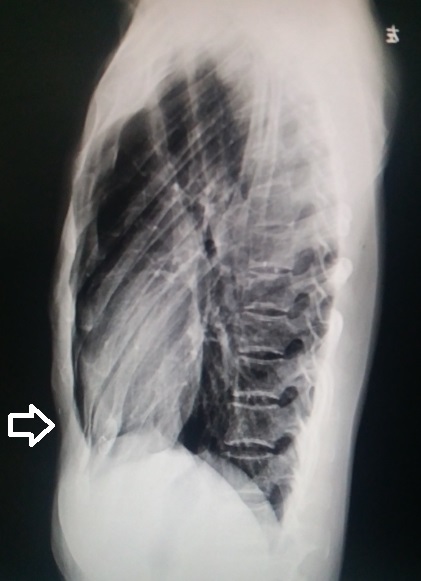

入院查体:胸壁表面大量陈旧性手术疤痕,其中正中一条,长约30cm,周围另有8个手术疤痕,长短不等(图1)。左前下胸壁局限性凹陷,明显低于周围结构,可见心脏搏动(图2,3)。心脏听诊未闻及杂音。X线检查提示前下胸壁凹陷畸形(图4)。心电图未见异常。

图4,前下胸壁凹陷畸形。